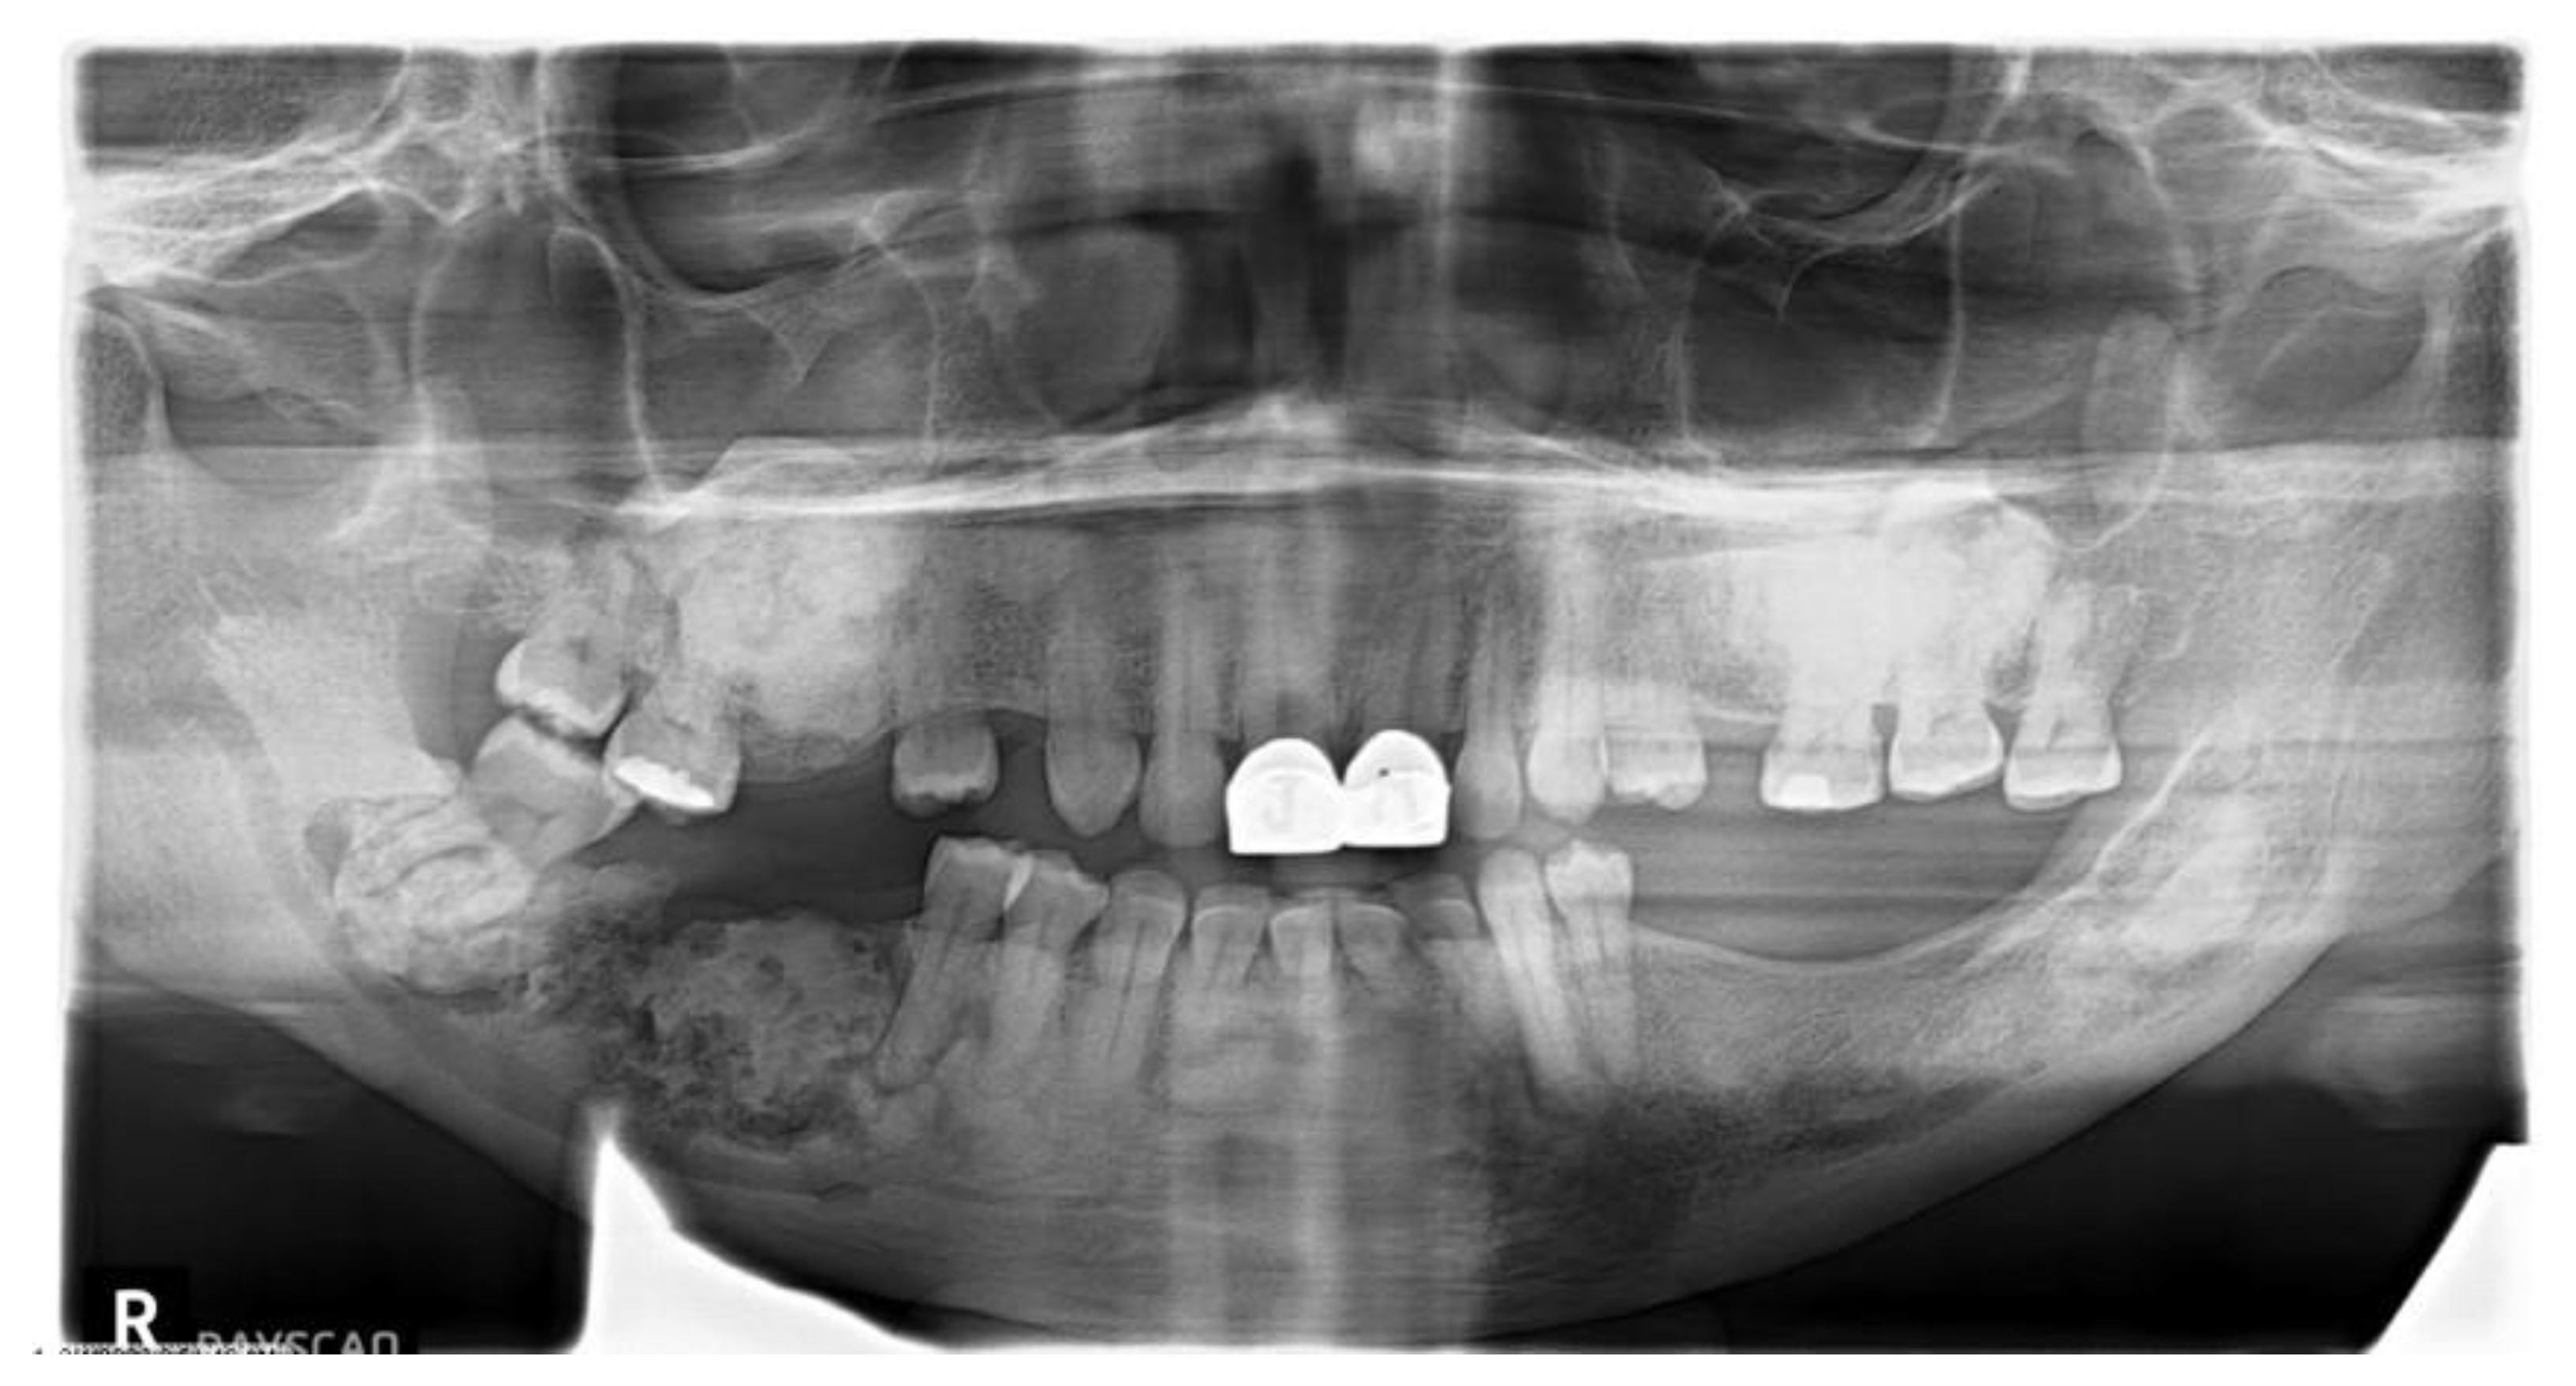

Types of COD